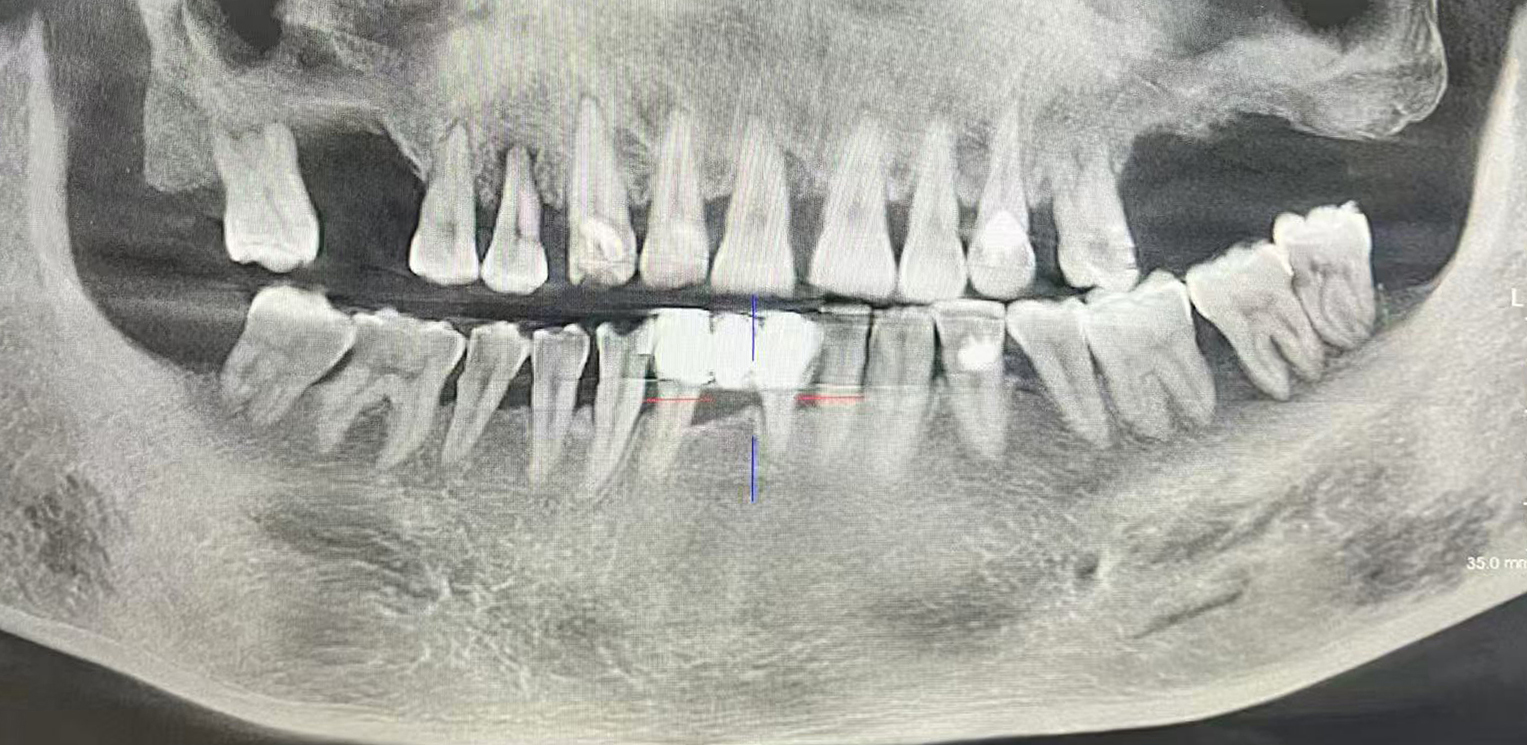

接诊的是到城阳人民医院坐诊的北京大学人民医院皇冠篮球比分网_澳门现金网-球探体育:医院口腔科宋玲主任,检查后发现,纪先生的口腔状况很不乐观:牙结石堆积如山,牙龈红肿退缩,已有4颗牙齿脱落,剩余牙齿也有不同程度的松动,有的甚至发生牙周-牙髓联合病变,拍片显示多颗牙齿牙槽骨吸收至根长1/2,有的甚至达2/3——这意味着支撑牙齿的“地基”严重流失。

(口腔科影像照片)牙周病: